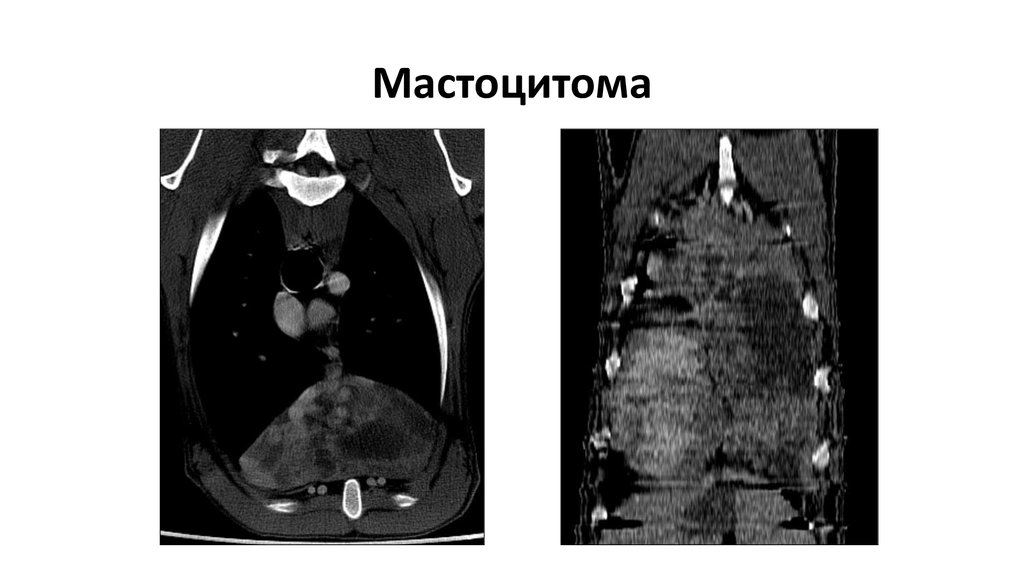

Мастоцитома

40. Мастоцитома